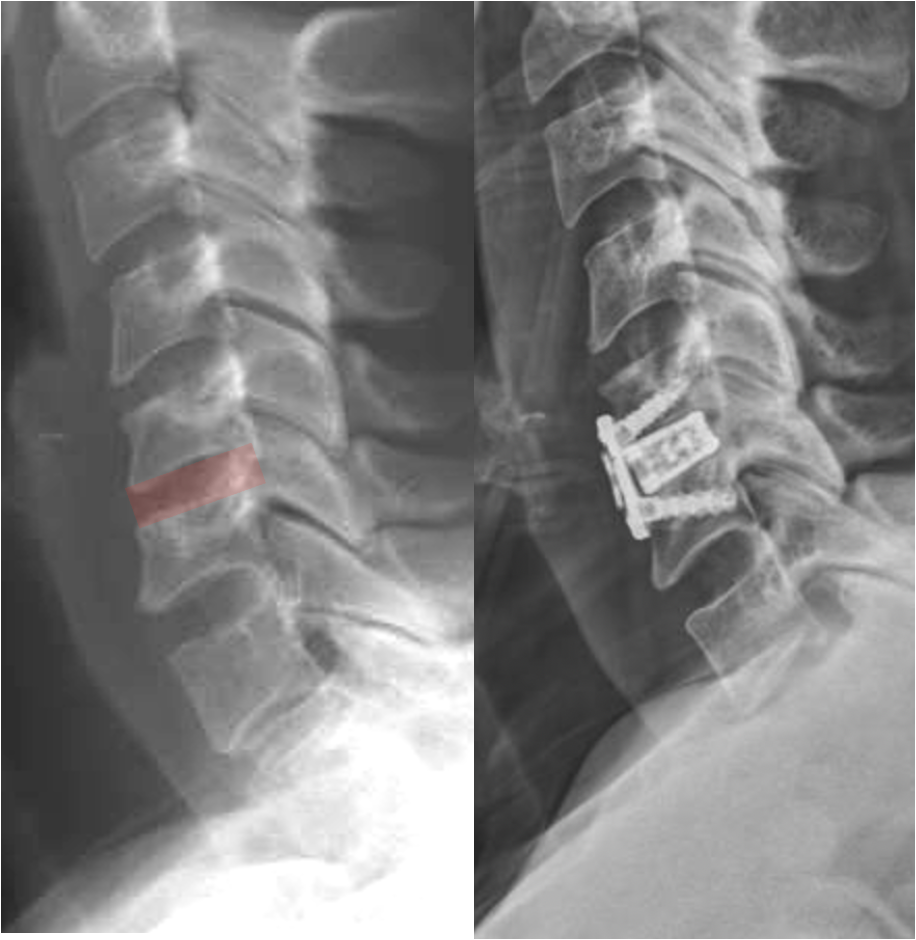

Comparison of spinal X-rays showing normal alignment on the left and surgical intervention with spinal hardware on the right.

Benefits of ACDF Surgery

ACDF surgery can significantly improve symptoms caused by nerve or spinal cord compression.

Potential benefits include:

• Relief of arm pain and nerve symptoms

• Improvement in numbness or tingling

• Recovery of strength in the arm or hand

• Stabilization of the cervical spine

• Prevention of further nerve compression

Many patients experience rapid improvement in arm pain after surgery.